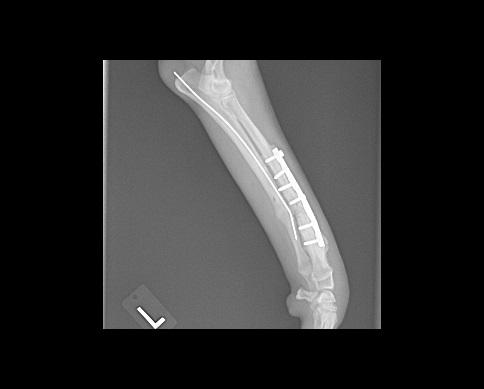

His radius and ulna were both fractured, the two bones that correspond with our forearm. The best repair for this type of fracture is a metal plate. Drs. Yoder and Coughlin placed a pin down his ulna to align the bones and assist in stabilizing the area. Then they used screws to place a metal plate on his radius to hold the two pieces of bone close together and prevent movement. For the first month Loki wore a splint to help keep everything stable in such an active puppy. In eight weeks he was walking with a slight limp and was getting back to his normal activities.

These images are post surgery checking for appropriate pin placement and alignment of the fracture.